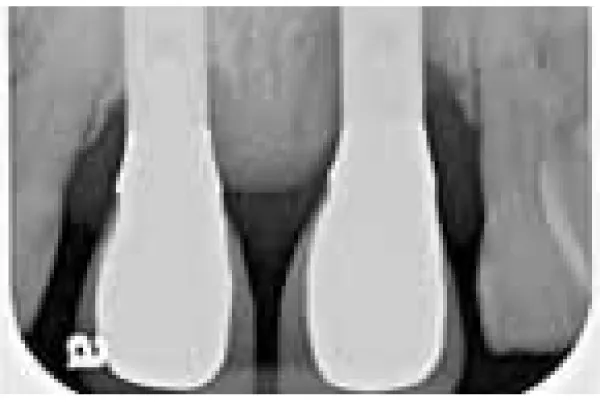

The third clinical cases was a 47 year old male patient with a dental implant [21], placed in the frontal region of the maxilla. More precisely, implant compensates for the naturally lost central left incision. After three months of dental implant placement, the patient began to complain of pain coming from the area where the dental implant was placed. The marginal gingiva in that region was oedematous and hyperemic, and blood was drained during the process of probing. The peri-implant mucositis was detected. On the figures 21-25 the situation before the surgery treatment was seen.

The tenth clinical case was a 30 year old female patient. Before a period of 7 months she received dental implant due to a missing of the frontal right central incision 11. The patient was in excellent health and without allergy to any medication. An X-ray was made, showing changes in bone tissue around the dental implant. Around dental implant (from the mesial and distal side) a bone defect was detected, which occurred after a period of seven months. During the probing around the dental implant, the probe went down 4 mm in pocket from the mesial side and 3 mm from the distal side. The greater loss of bone tissue was detected from the mesial side of the dental implant than from the distal side. The patient was identified to have peri-implant disease (Figure 34).